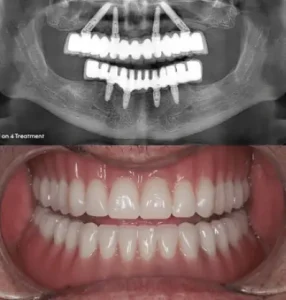

Usually, full mouth dental implant treatments use four, six or eight implants per single jaw. The increased number of implant screws provides more stability to the attached fixed bridge that replaces the patient’s teeth, though some patients can lack jawbone density for eight or six implants per jaw.

The process starts with a full dental consultation, during which dentists check the patient's oral health and talk about their specific wants and goals. Diagnostic imaging, such as panoramic X-rays, may be used at this first visit to check the health of the jawbone and structures nearby. With this information, the dentist can make a personalised treatment plan for you, discussing options such as implant systems and any necessary dental preparation.

Stage 2: Fixing implants

The next stage after creating the treatment plan is to surgically place the implants. Dental doctors insert titanium screws into the jawbone using tiny incisions. For the patient's comfort, we apply anaesthesia during this process. The screws hold the new teeth in place. Once the implants are in, the bone needs to heal for a few months so that it can join with the implants, making the tooth stable and strong.

Stage 3: Attachment of permanent teeth

Total implants required for complete mouth restoration

All on 4 implants

For minimally invasive upper and lower jaw restoration, all on 4 implants are popular. A permanent bridge is supported by four strategically placed titanium implants. All on 4 is a realistic choice for many patients since it requires less bone density than standard implants. This dental surgery allows patients to attain a complete smile with fewer implants, making it an attractive alternative for people seeking cheap choices in Turkey.

All on 6 implants

For stability and support, you should consider an All on 6 implant. Six dental implants secure a full-arch prosthesis for lifespan and function. Multiple implants improve weight distribution and can benefit patients with significant bone loss or those requiring a more durable treatment. This treatment is slightly more expensive than All on 4, but it offers extra protection and peace of mind that are worth considering.

All on 8 implants

Eight implants support a full set of teeth with the All on 8 implant system, increasing stability. This treatment is best for people with substantial bone loss or who seek the most reliable dental restoration. Extra implants stabilise and make eating and speaking more natural. The extra security and comfort of this treatment make it worth the higher cost for many people.